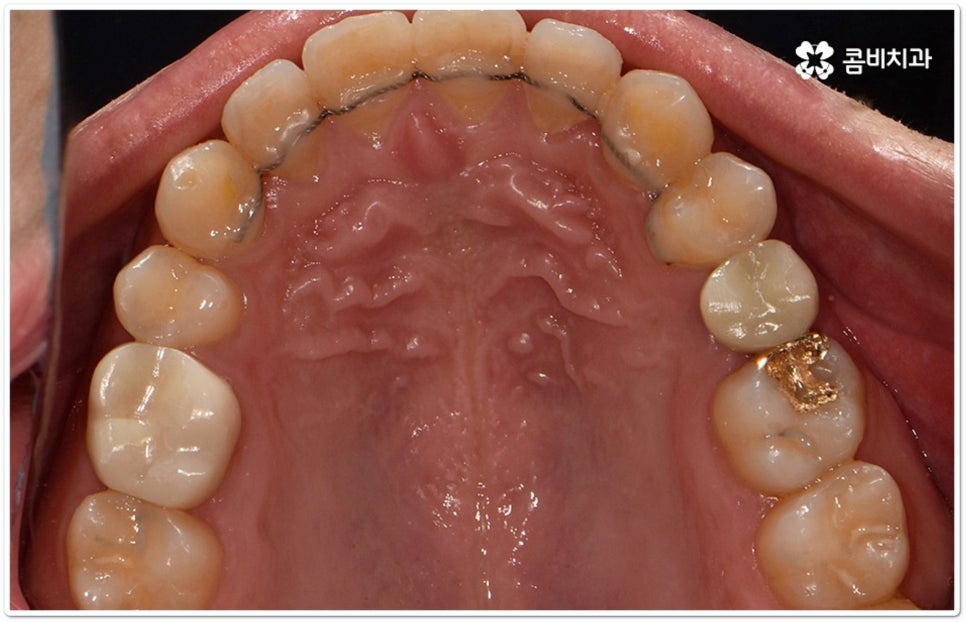

예를 들어 심미성도 중요하지만 가격적인 부담을 좀 더 줄일 수 있는 방법이 없을까 싶을 때는 일반 세라믹 교정을 이용하여 교정 치료를 진행할 수 있고 세라믹 브라켓보다 더 심미성이 뛰어나면서도 불편함이나 이물감이 크지 않은 방법은 무엇일까 궁금할 때는 겉으로 보이지 않는 설측교정의 단점을 보완한 콤비교정을 고려해 볼 수 있는 거예요. 이와 같이 환자분들 상황에 맞게 도움을 받을 수 있는 여러 장치들이 있으니 환하고 밝은 미소에 대한 로망이 계속 있으셨다면 더이상 망설이지 말고 정밀 검진과 상담부터 차근차근 진행해 보시길 권유드리고 있습니다.